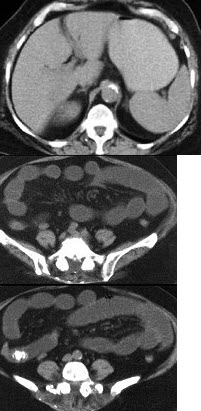

男,30岁,有胆结石病史,近日腹痛、腹胀,CT检查如图,应诊断为( )

A:胆石症

B:胆石性肠梗阻

C:肠结核

D:小肠克罗恩病

E:小肠淋巴瘤